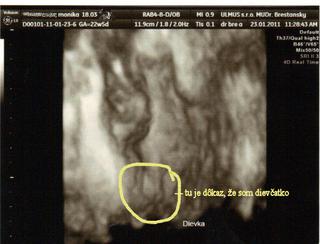

@monika0001 ako je dobre vidiet, ze je to dievcatko...som si nemyslela, ze sa to da az tak dobre... ked clovek cita ako sa lekari uz viackrat pomylili a povedali, ze dievcatko a zrazu to bol chalan....

my sme pri prvom sice nemali pochybnosti, ale to preto, ze predsa len pipik trcal dost vela... 😀 Ale teraz vidim, ze aj dievcatko sa da urcit velmi presne.... tak sa tesim...na 3D/4D idem 1.2.

@saeda - ja som to takto isto videla v 17tt keď mi to prvý raz povedal môj doki 😀

ale ja som o tom ani nepochybovala od začiatku :-P akosi som to tak cítila, že to bude Stellinka.... 😉

@saeda - na normálnom.. a normálne lepšie ako na tomto 4D.. tu mi to musel ukázať 😅